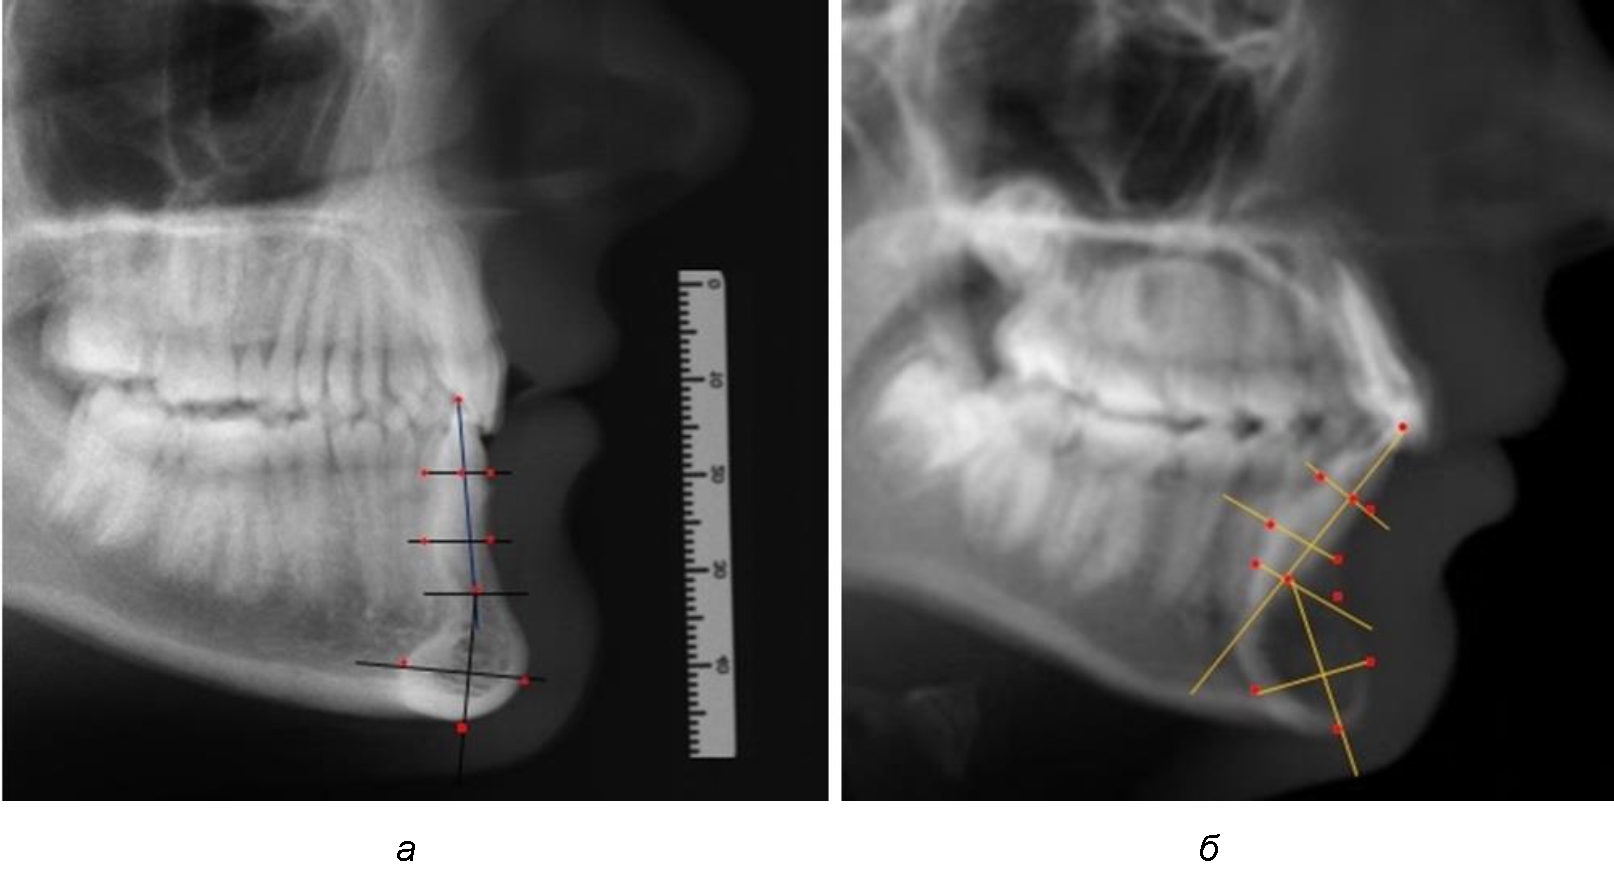

Предложен метод исследования зубочелюстных сегментов, который проводился на масштабированных фотографиях, и в программе Microsoft PowerPoint обозначались точки с последующим построением линий, необходимых для измерения по вертикали и сагиттали.

На режущем крае нижнечелюстного резцового сегмента устанавливалась точка, обозначаемая как IsL.

Определяли положение цервикальных точек резцов на вестибулярной и лингвальной поверхностях, которые соединяли цервикальной линией. Условная срединную вертикаль зуба соединяла резцовую точку IsL с серединой цервикальной линии и, как правило, доходила до апикальной точки, которую обозначали как Ap. Линия IsL–Ap определяла высоту зубоальвеолярной части резцового нижнечелюстного сегмента. Определяли высоту коронки и корня зуба. Кроме того, на вестибулярной поверхности зубочелюстного сегмента отмечали точку наибольшей вогнутости альвеолярной части, которая обозначалась как супраментальная точка Downs (Bsm). Измерялось расстояние IsL–Bsm, которое служило для определения проекции супраментальной точки Downs на язычную поверхность сегмента и обозначалась как точка Bsm'.

Проекцию верхушки корня резца на кость обозначалась как точка B нижнего апикального базиса по Schwarz. Соединяли апикальную точку с точкой нижнечелюстного апикального базиса линией, которая доходила до язычной поверхности подбородочного выступа и определяла положение точки B'. Таким образом, в зубоальвеолярной части сегмента выделялись две зоны: верхняя и нижняя, с последующим измерением по вертикали. При этом, как правило, верхняя зона была представлена компактной костной тканью, а в нижней зоне определялось наличие губчатой ткани между компактной пластинкой и стенкой альвеолы.

На нижнем контуре подбородочного выступа определяли положение ментальной точки Me. Линия, соединяющая апикальную точку с ментальной, определяла высоту подбородочного выступа тела нижней челюсти. Высота зубочелюстного сегмента IsL–Ме измерялась от резцовой до подбородочной точки. Вертикальная линия Ap–Me делила подбородочный выступ на две части: переднюю и заднюю (рис. 1).

Рис. 1. Ориентиры для исследования нативных препаратов (а) и рентгенограмм (б) резцового нижнечелюстного сегмента

Сагиттальные размеры зубоальвеолярной части сегмента определялись между точками Bsm и Bsm', в апикальной части сегмента – B и B'. В подбородочной части сегмента из передней выступающей точки подбородка Pog проводили линию перпендикулярно к линии Ар–Ме с определением точки Pog'. Расстояние Pog–Pog' определяло ширину подбородочного выступа.